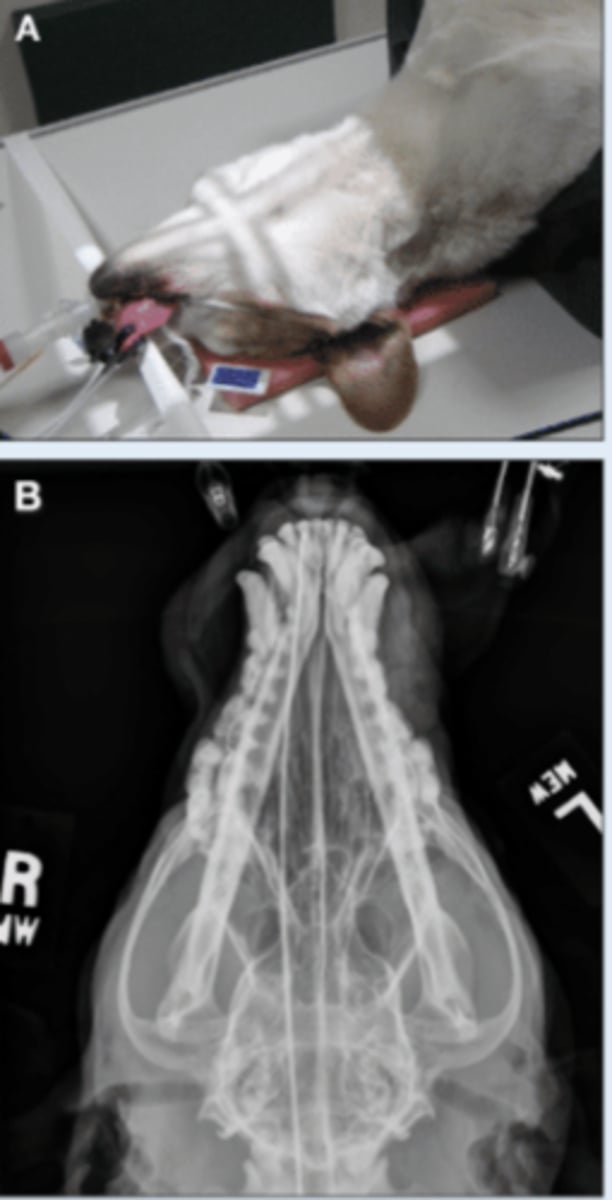

SM Animal Skull- VD image

• Patient in dorsal recumbency

• Markers to indicate laterality

SM Animal Spine Lateral

SM Animal Spine VD